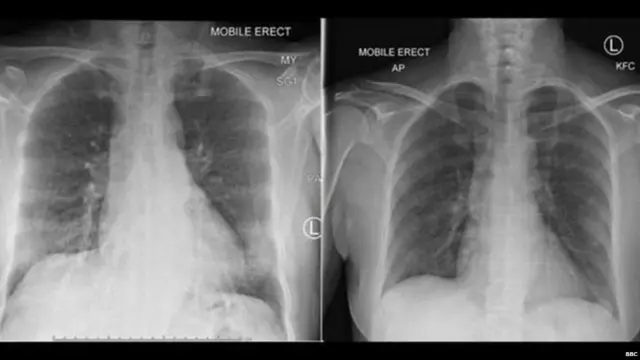

ઇમેજ સ્રોત, PETER DOHERTY INSTITUTE

એક તરફ કોરોના વાઇરસનો ચેપ લાગ્યાના કેસની સંખ્યા ઝડપભેર વધી રહી છે ત્યારે બીજી તરફ ઘણા લોકો તેના ચેપમાંથી મુક્ત થયાના સમાચાર પણ છે.

શોધકર્તાઓનું કહેવું છે કે ચેપ લાગ્યો હોય તેવા અનેક લોકોને બધાથી અલગ, એકલા રાખવામાં આવ્યા હતા અને હવે તેઓ સ્વસ્થ થઈને પોતપોતાના ઘરે પાછા ફર્યા છે. તે દર્શાવે છે કે માનવશરીરની રોગપ્રતિકારક વ્યવસ્થા આ ચેપ સામે લડવાનું જાણે છે.